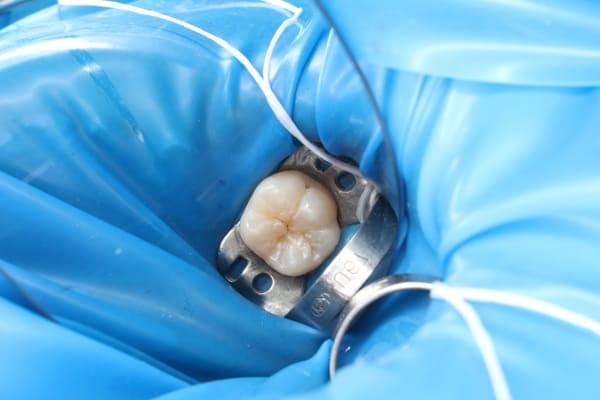

Поява перших постійних зубів, а це шості зуби, відбуваються, коли дитина ще не може, як слід провести їх гігієну та попіклуватись про їх здоров’я. Тому, на жаль вони і вражаються карієсом досить швидко. Пацієнт ще маленький – 6 років, а лікування потребує дорослого: зі знеболенням та ізоляцією. Саме таке і було проведене в даному випадку: зуб очищений від інфікованих тканин, відновлений фотополімерним матеріалом і готовий довго служити юному господарю.